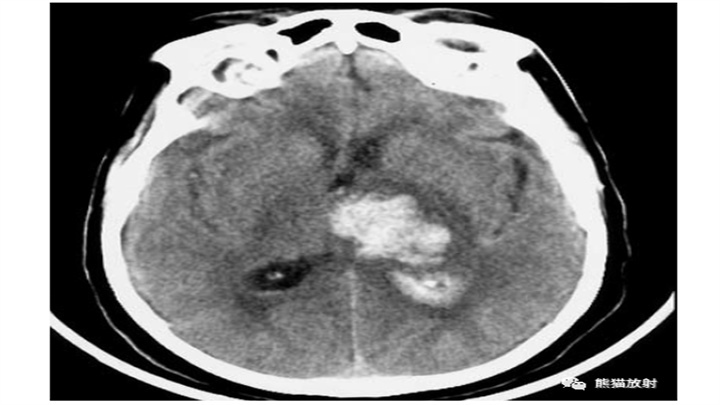

大量脑出血,累及左丘脑和基底节。明显的占位效应(中线结构向对侧明显移位)和脑室积血(同侧脑室变扁,右侧枕角积血)。然而,像往常一样,腹周水肿的数量仅限于周围边界。患者在数小时后死亡。